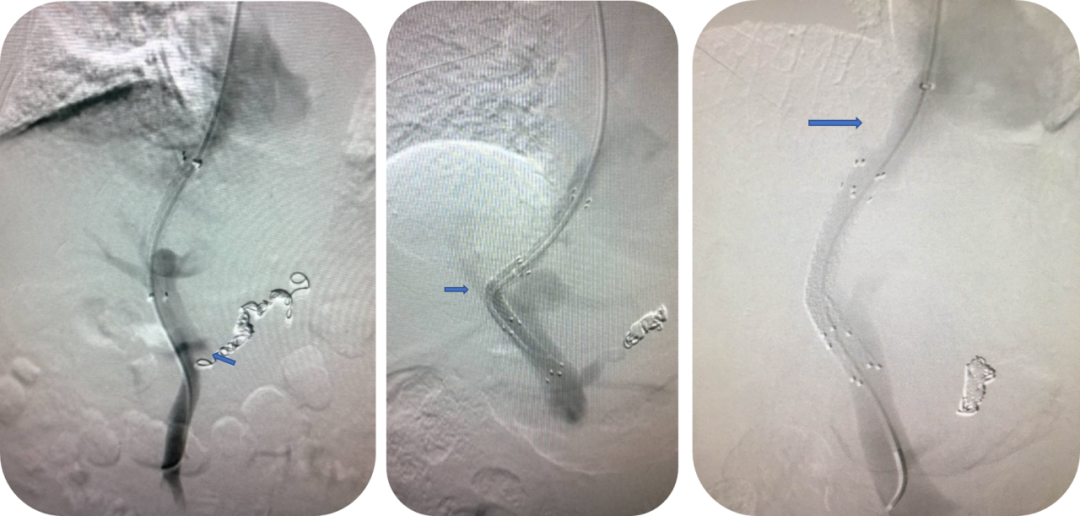

复杂门静脉病变的拓展治疗

门静脉血栓(PVT)

联合使用 AngioJet、Straub 吸栓系统 经 TIPS 入路清除肠系膜上静脉血栓;

近年采用 Indigo 抽吸导管 成功处理肝移植术后门静脉血栓。

肝硬化门静脉血栓—TIPS联合AngoJet

肝硬化门静脉血栓—TIPS联合Straub吸栓

近期尝试Indigo抽吸导管用于肝移植术后门静脉血栓